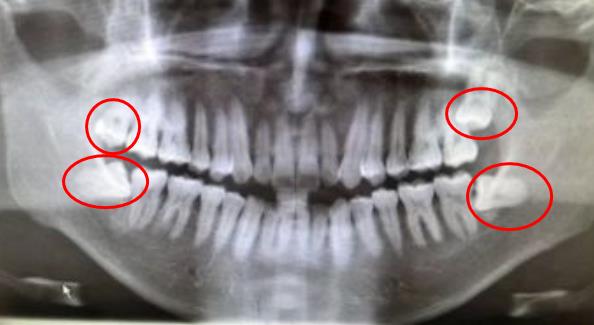

智齒,通常在16歲以後萌出的牙齒,位置靠裏,加上萌出時間晚,不好找自己的地盤,隻能在夾縫裏求生存,這就是大部分智齒位置不正,造成智齒周圍組織發炎,需要拔除的原因。不過在決(jue) 定拔牙後,還需要選擇合適的醫院才行。 (自行判斷有無智齒的方法:從(cong) 正...

(自行判斷有無智齒的方法:從(cong) 正中的門牙向左或者向右數,如果有8顆,那第8顆就是智齒)